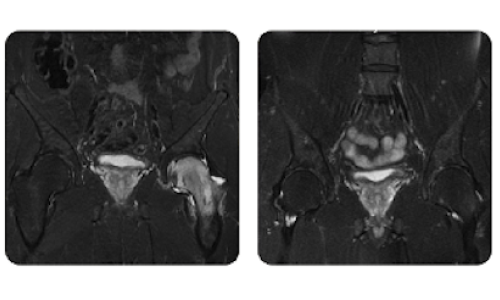

I progressi dei nostri pazienti, misurati prima e dopo la terapia iperbarica, riflettono l'efficacia e l'impatto positivo del trattamento. Scopri i risultati documentati della terapia iperbarica presso la clinica Hyperbarium Oradea, basati su valutazioni cliniche e dati oggettivi che evidenziano miglioramenti significativi in diverse condizioni.